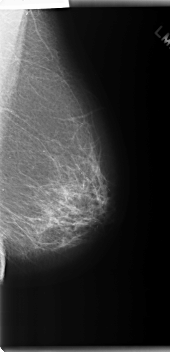

C_0202_1.RIGHT_CC

LEFT_CC LINES 5976 PIXELS_PER_LINE 3008 BITS_PER_PIXEL 12 RESOLUTION 50 NON_OVERLAY